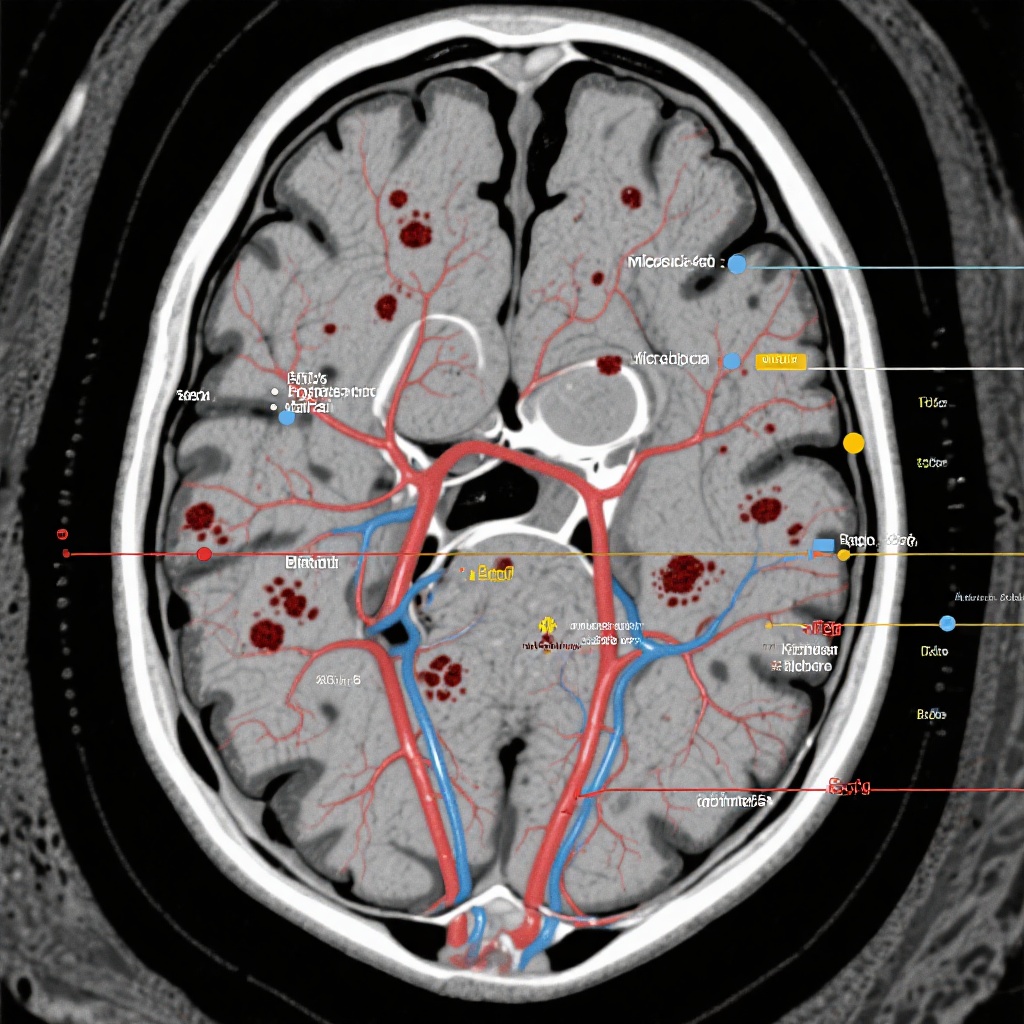

- Xuất huyết não mới (ICH): Được định nghĩa là sự kiện chảy máu có đường kính lớn hơn 10 mm.

- Vi chảy máu não (CMBs): Được định nghĩa là các vùng nhỏ, tròn có tín hiệu không đồng đều trên hình ảnh có trọng số độ nhạy (SWI) hoặc hình ảnh gradient hồi âm (GRE) có trọng số T2*, có đường kính 10 mm trở xuống.

- Siderosis nông dưới biểu bì (CSS): Được đặc trưng bởi các vết máu sản phẩm tuyến tính trong không gian dưới màng nhện hoặc lớp nông của vỏ não.

Xuất huyết não mới xảy ra ở 5,1% bệnh nhân trong nhóm apixaban so với 6,4% trong nhóm aspirin. Sự khác biệt về số lượng nhỏ có lợi cho apixaban, mặc dù nó không đạt ý nghĩa thống kê (P > .05).

Sự phát triển của vi chảy máu mới được quan sát ở 7,8% nhóm apixaban và 10,8% nhóm aspirin. Một lần nữa, không có bằng chứng cho thấy chống đông máu bằng apixaban dẫn đến gánh nặng cao hơn của các dấu hiệu chảy máu mạch máu nhỏ so với liệu pháp chống tiểu cầu tiêu chuẩn.

Siderosis nông dưới biểu bì mới, thường là dấu hiệu của bệnh mạch máu não amyloid hoặc chảy máu dưới màng nhện trước đó, được tìm thấy ở 7,7% nhóm apixaban và 12,9% nhóm aspirin. Kết quả này đặc biệt đáng chú ý vì CSS là một yếu tố dự báo mạnh mẽ của ICH có triệu chứng trong tương lai, và việc không tăng ở nhóm apixaban hỗ trợ hồ sơ an toàn của nó.